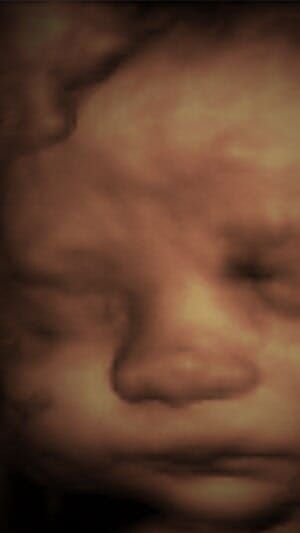

- Ultrasonido detallado y completo durante el embarazo en 2D, 3D y 4D

- Detección de defectos, síndromes y malformaciones fetales